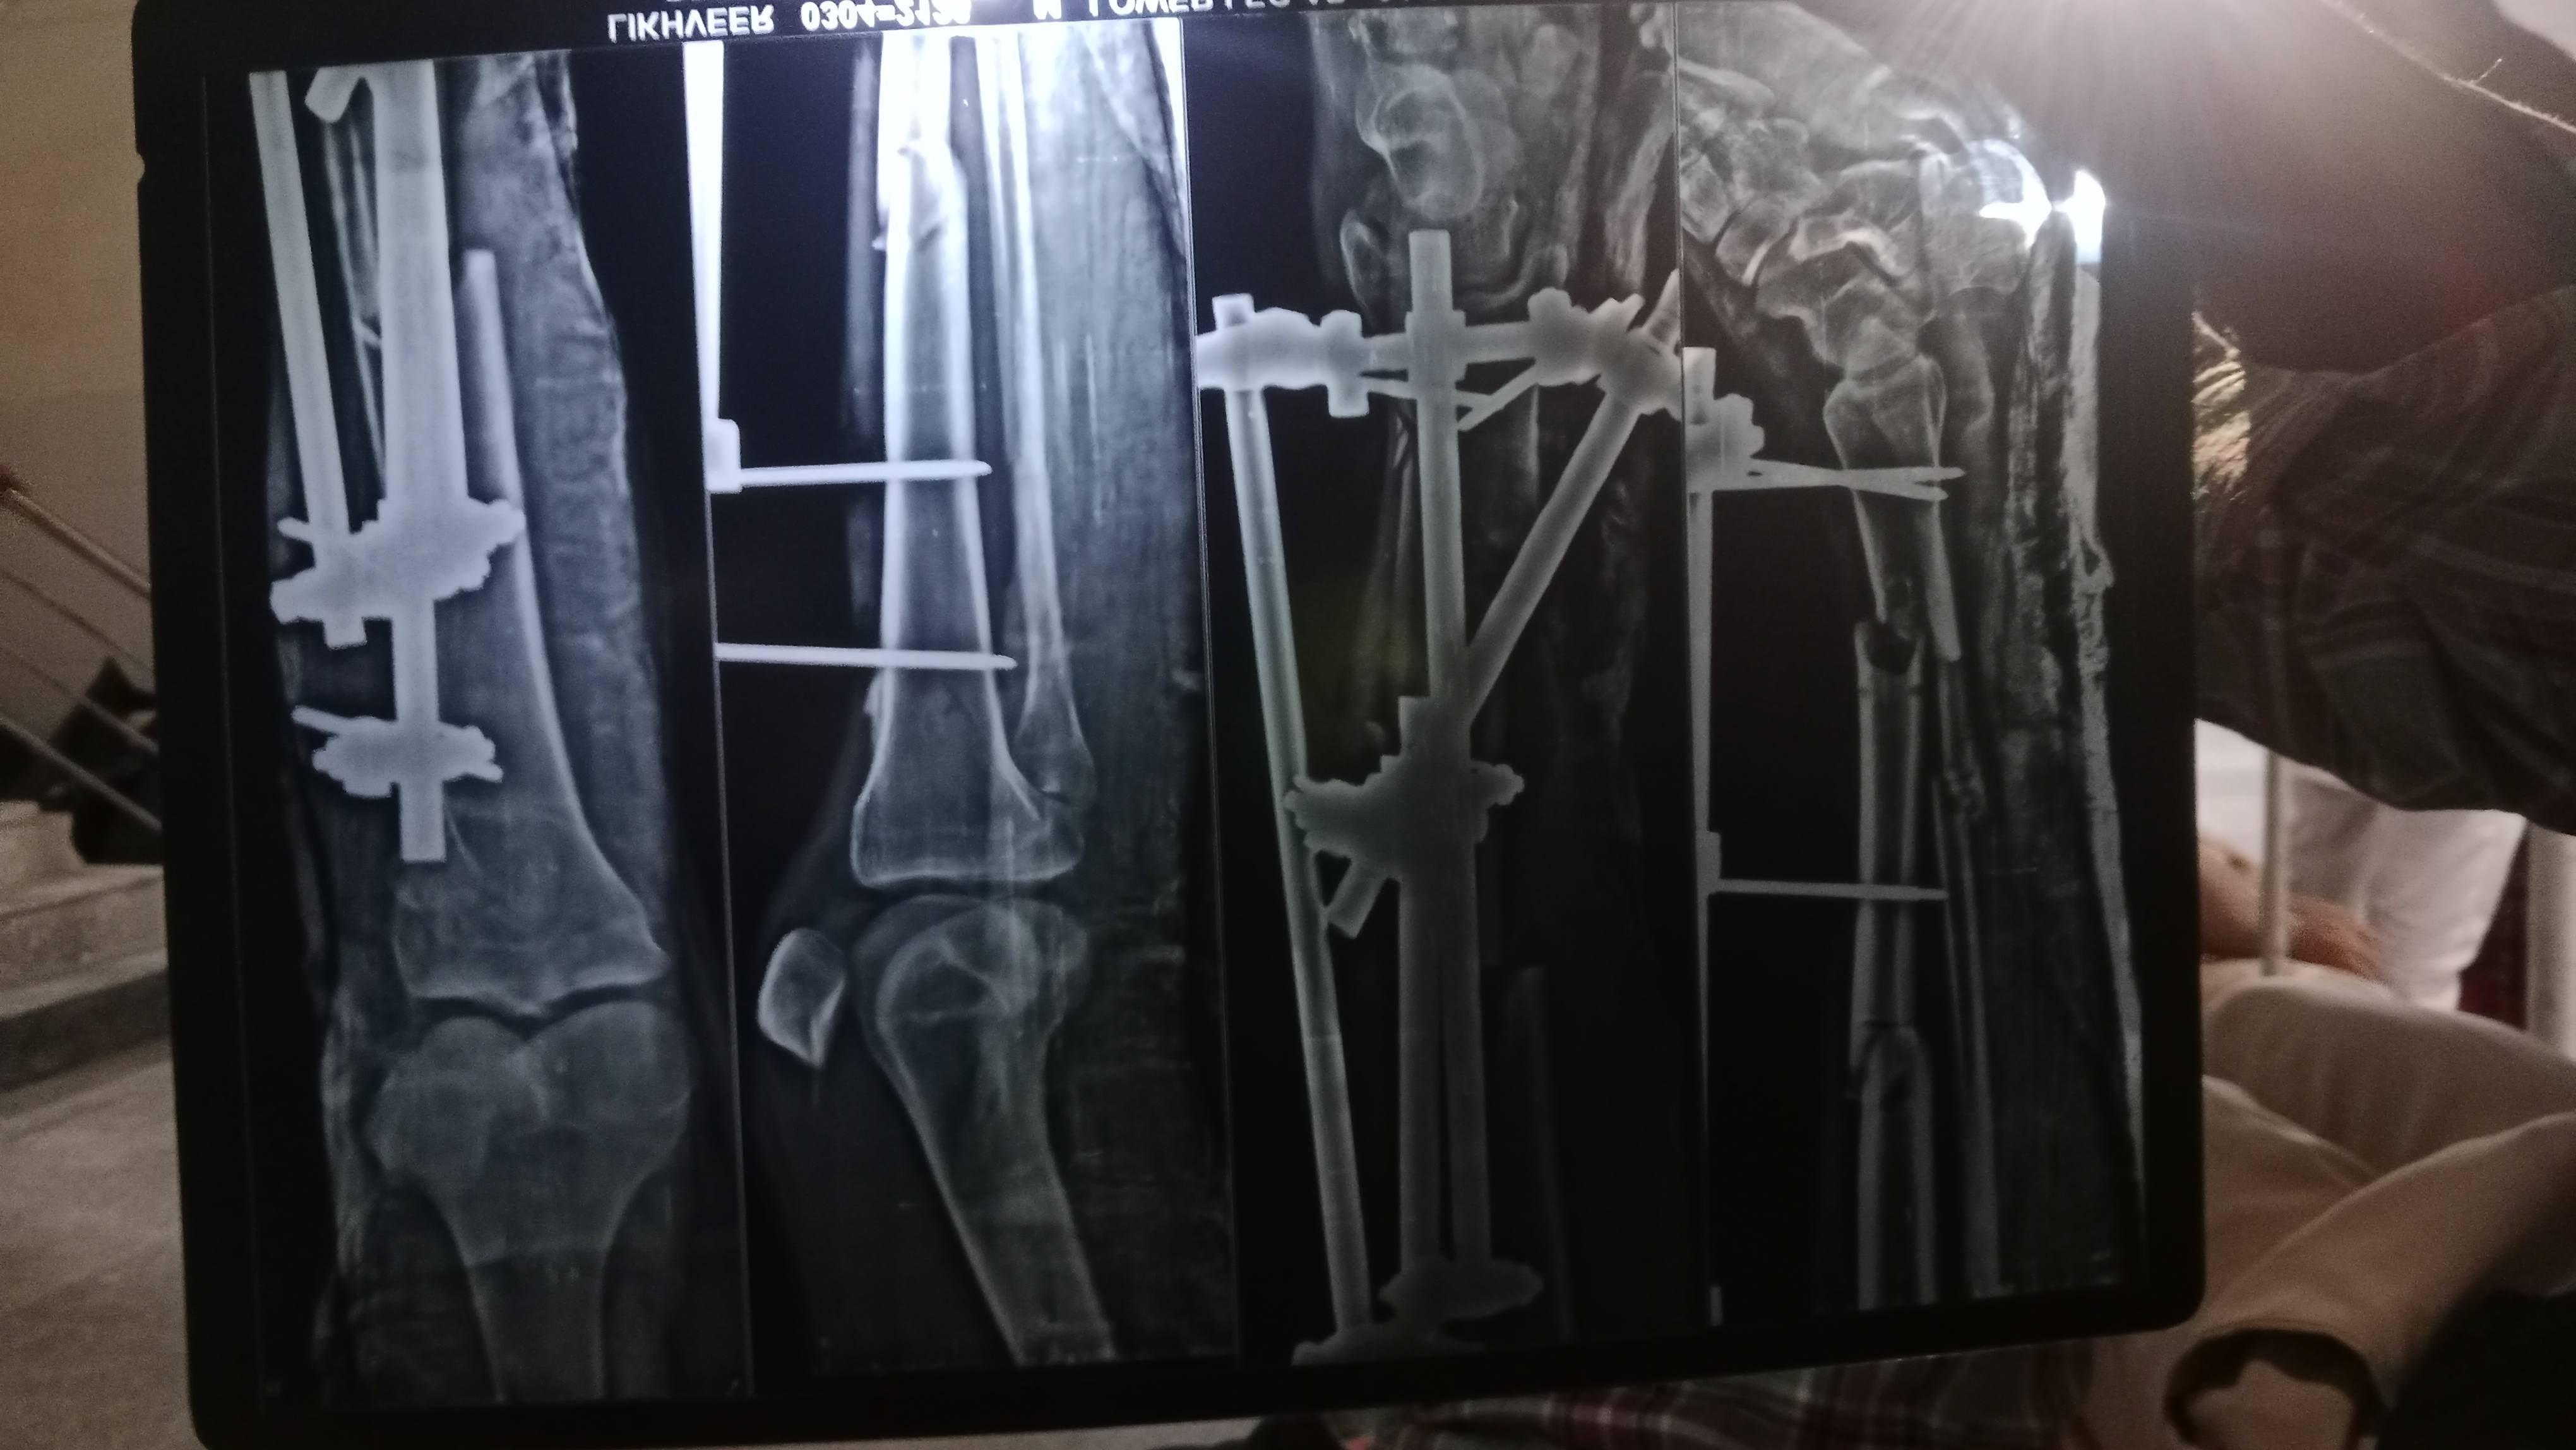

Without operation how to joined soulder. Tell me all details

Thia is not proper joined it . Pain is very much how to solve it